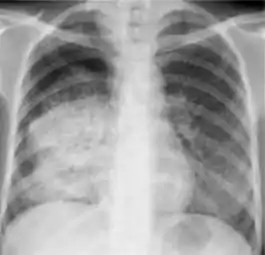

Chest X-ray findings that can suggest inactive TB

This category includes findings that are suggestive of prior TB, that is inactive. Assessments of the activity of TB cannot be made accurately on the basis of a single radiograph alone. If there is any question of active TB, sputum smears must be obtained. Therefore, any applicant might have findings grouped in this category, but still have active TB as suggested by the presence of signs or symptoms of TB, or sputum smears positive for AFB.[2]

The main chest X-ray findings that can suggest inactive TB are:[2]

1. Discrete fibrotic scar or linear opacity—Discrete linear or reticular densities within the lung. The edges of these densities should be distinct and there should be no suggestion of airspace opacification or haziness between or surrounding these densities. Calcification can be present within the lesion and then the lesion is called a "fibrocalcific" scar.

2. Discrete nodule(s) without calcification—One or more nodular densities with distinct borders and without any surrounding airspace opacification. Nodules are generally round or have rounded edges. These features allow them to be distinguished from infiltrates or airspace opacities. To be included here, these nodules must be noncalcified. Nodules that are calcified are included in the category "OTHER X-ray findings, No follow-up needed".

3. Discrete fibrotic scar with volume loss or retraction—Discrete linear densities with reduction in the space occupied by the upper lobe. Associated signs include upward deviation of the fissure or hilum on the corresponding side with asymmetry of the volumes of the two thoracic cavities.

4. Discrete nodule(s) with volume loss or retraction—One or more nodular densities with distinct borders and no surrounding airspace opacification with reduction in the space occupied by the upper lobe. Nodules are generally round or have rounded edges.

5. Other—Any other finding suggestive of prior TB, such as upper lobe bronchiectasis. Bronchiectasis is bronchial dilation with bronchial wall thickening.